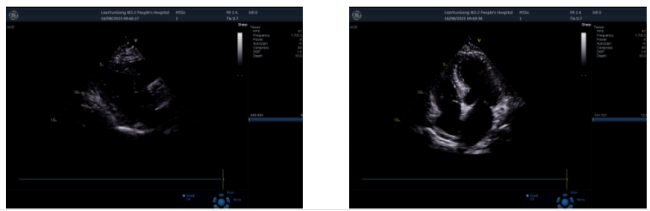

图6. 第一跖趾关节浅表超声2025-08-16 心脏超声:左房增大;室间隔增厚;主动脉瓣、二尖瓣、三尖瓣少量反流;左室舒张功能减低(图7)。

图7. 心脏超声